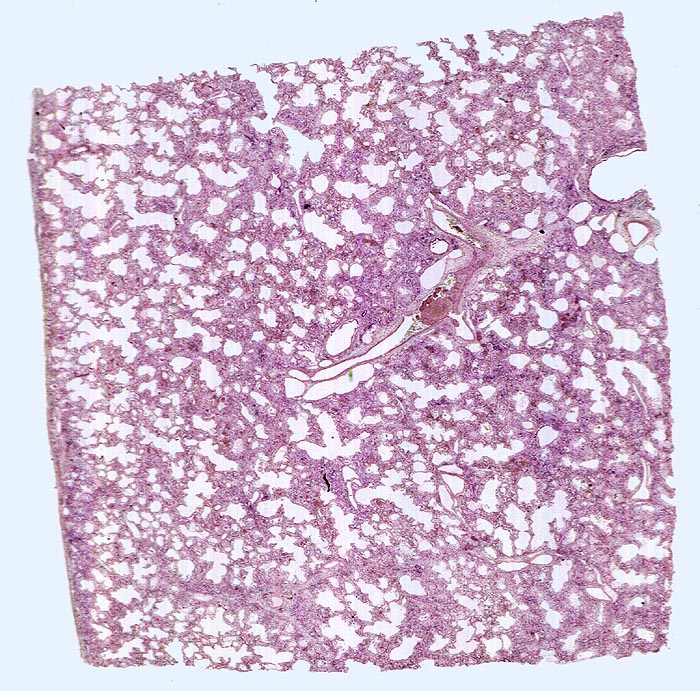

Diffuser Alveolarschaden, exsudatives und proliferatives Stadium

In der Übersicht ist eine diffuse Verbreiterung der Alveolarsepten erkennbar.

Makroskopischer Lungenbefund: schwere, wässrige und verfestigte dunkelrote Lungen aus denen sich nur wenig Flüssigkeit auspressen lässt.

Hospitalisation wegen akuter nekrotisierender Pankreatitis. Am zweiten Hospitalisationstag entwickelt der Patient ein ARDS (Adult Respiratory Distress Syndrome) mit rasch progredienter Dyspnoe und Tachypnoe, sowie einer Hypoxämie, welche im Verlauf auf Sauerstoffgabe nicht mehr anspricht. Das Thoraxröntgenbild zeigt bilaterale diffuse Verschattungen. Der Patient verstirbt trotz Intensivmassnahmen am 9. Tag nach Spitaleintritt am Multiorganversagen.

Der diffuse Alveolarschaden ist das morphologische Korrelat des ARDS (klinischer Begriff).